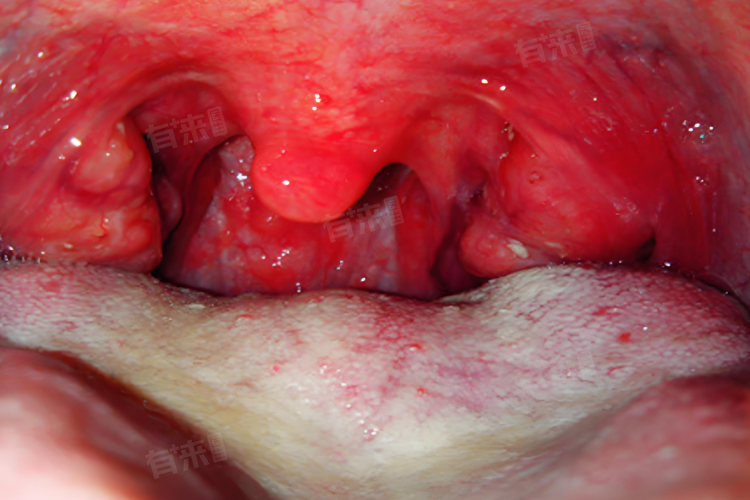

发炎的扁桃体会出现肿胀和红肿,有时扁桃体表面还会形成脓包。扁桃体肿大可能导致咽喉部位狭窄,加重咽痛和吞咽困难。